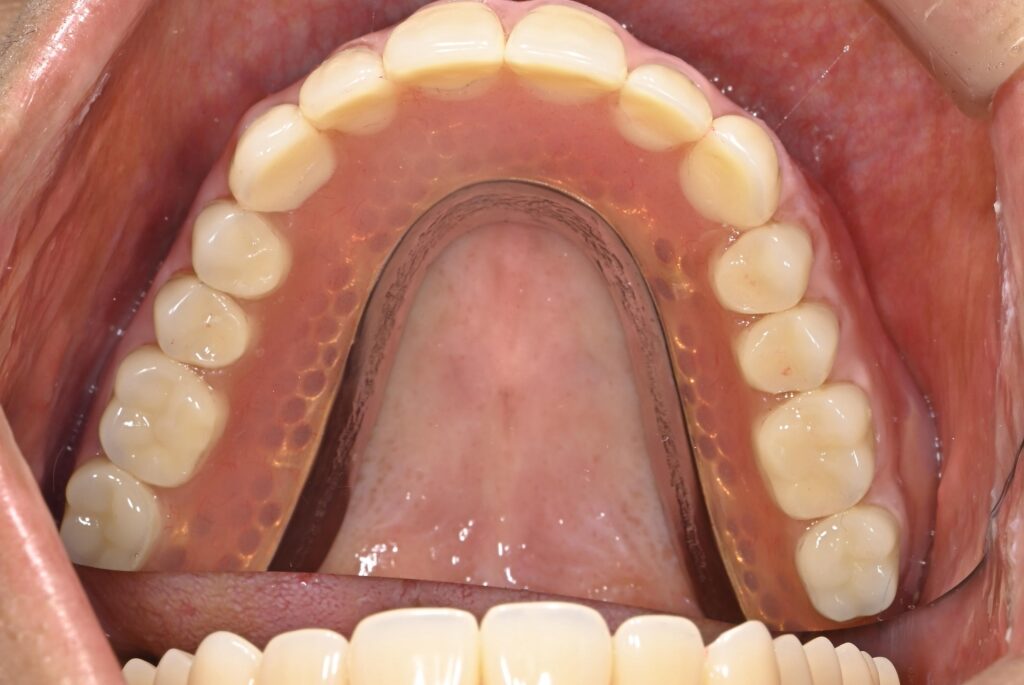

[症例4]

他院にてインプラント治療を行うが、上顎は4本中2本が脱落し、残りの2本のうち1本も膿が出て動揺している。

下顎は右下(向かって左下)3本のインプラントが脱落し、骨の吸収のため最埋入が出来ず、残りの歯を削ってオーバーデンチャー(歯とインプラントの上から被せる義歯)が装着されているが、うまく噛めない上に患者は見た目に不満を持っている。

当院では上顎は前医で埋入した1本のインプラントは保存し、上顎洞に骨を作って新たに3本のインプラントを埋入し、インプラントで支える面積を小さくした総義歯を作成した。

下顎は骨の足りなくなった右下に垂直的に骨を増やし、神経を損傷しないようにインプラントを2本埋入し、左下は古いインプラントを利用して新しいセラミック冠を作成、前歯は歯周治療後にセラミック冠を作成した。

よく噛めるようになり、見た目も審美的になったことで患者は大変満足している。

- 治療期間:2年7カ月

- 治療費:440万円

- 治療回数:50回